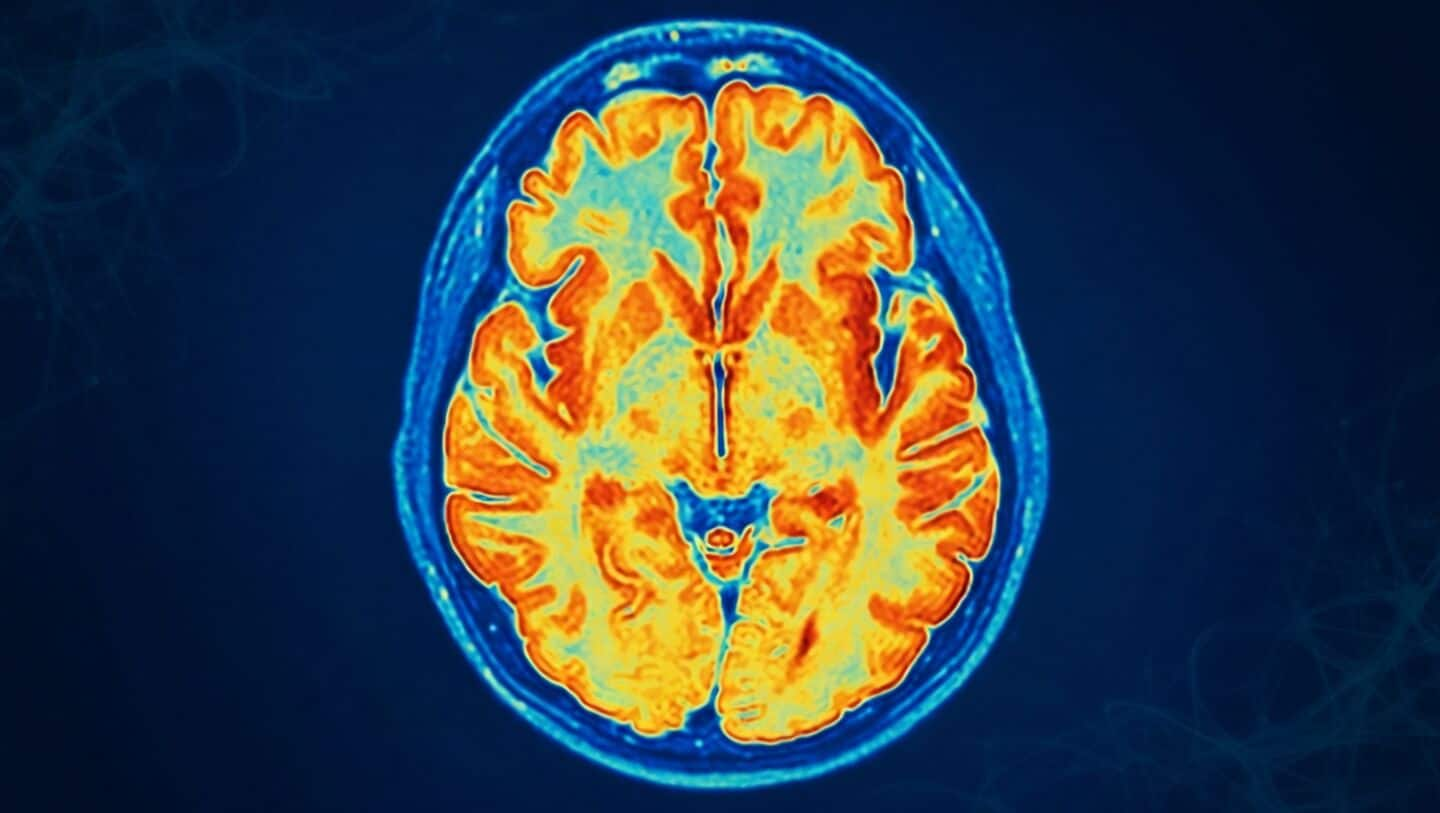

A newly discovered condition called ReNU2 syndrome is helping explain why some children face developmental delays, speech issues, and weak muscles.

It's linked to a rare gene mutation in the RNU2-2 gene that has to be inherited from both parents, and surprisingly, it accounts for about 10% of recessive neurodevelopmental disorder cases with a known genetic cause.